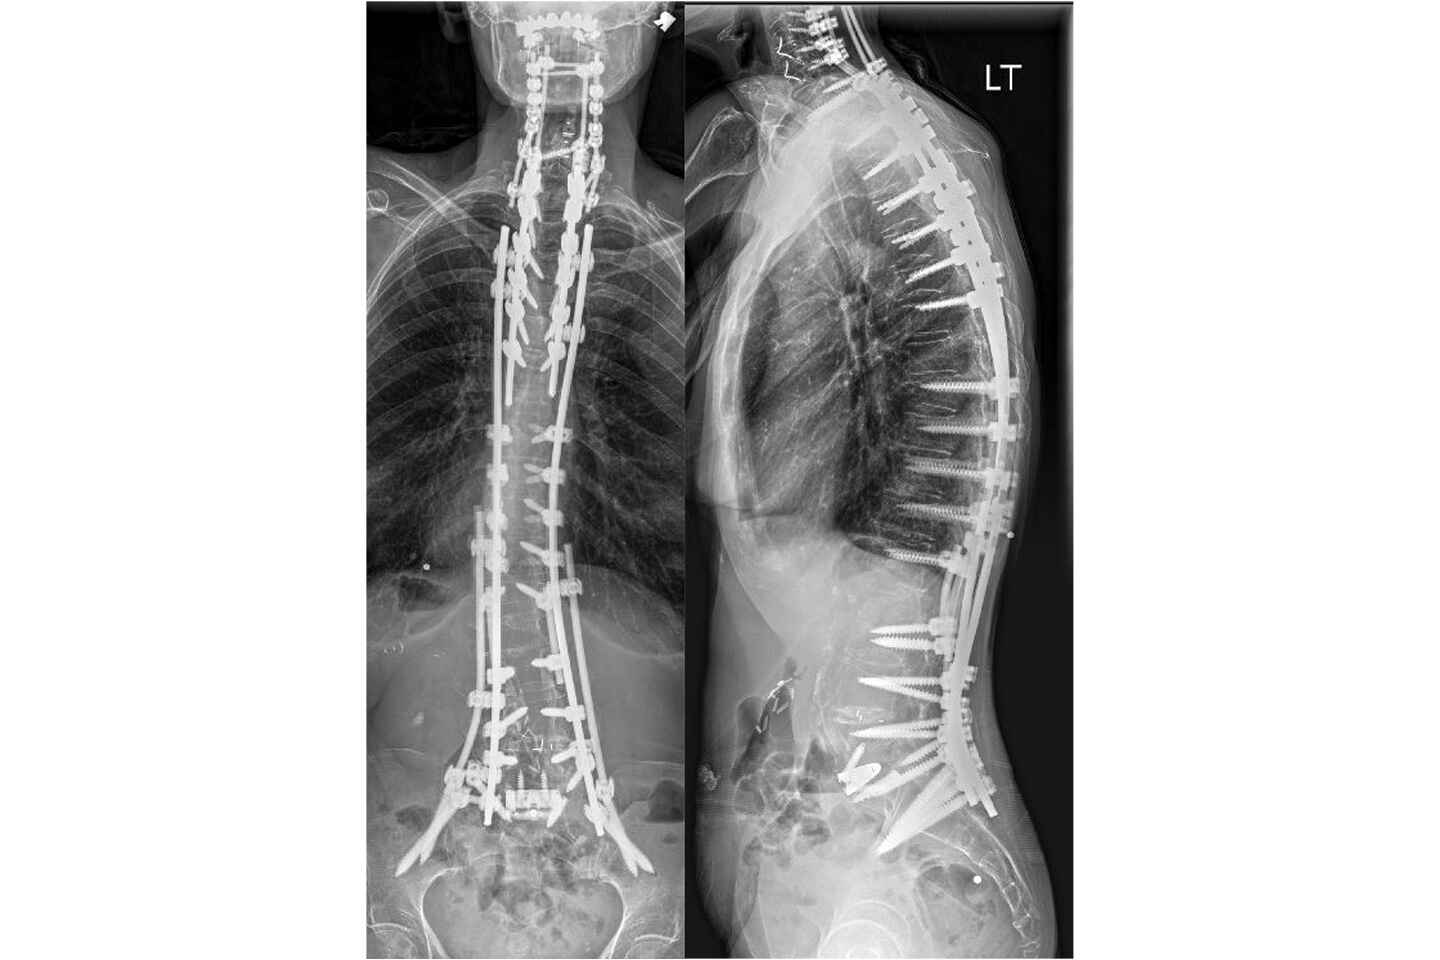

In a more extensive follow-up surgery two days later, Dr. Lau and colleagues revised her failed fusion construct from T4 to the pelvis and performed an L2 PSO to reshape and reconstruct the spine into a harmonious physiologic alignment.

The team implanted patient-specific, custom-made cobalt chrome rods—designed with novel AI technology—to stabilize the spine in its newly corrected position. Reconstructive plastic surgeon Michael S. Margiotta, MD, performed the complex spine closure.

At the patient’s three-month follow-up, she reported that her back felt “great,” with essentially no pain. Unexpectedly for both her and her neurologist, she also regained the ability to walk independently despite her MS.

X-rays taken three months postoperatively showing resolution of the spinal deformity. Source: NYU Langone Health